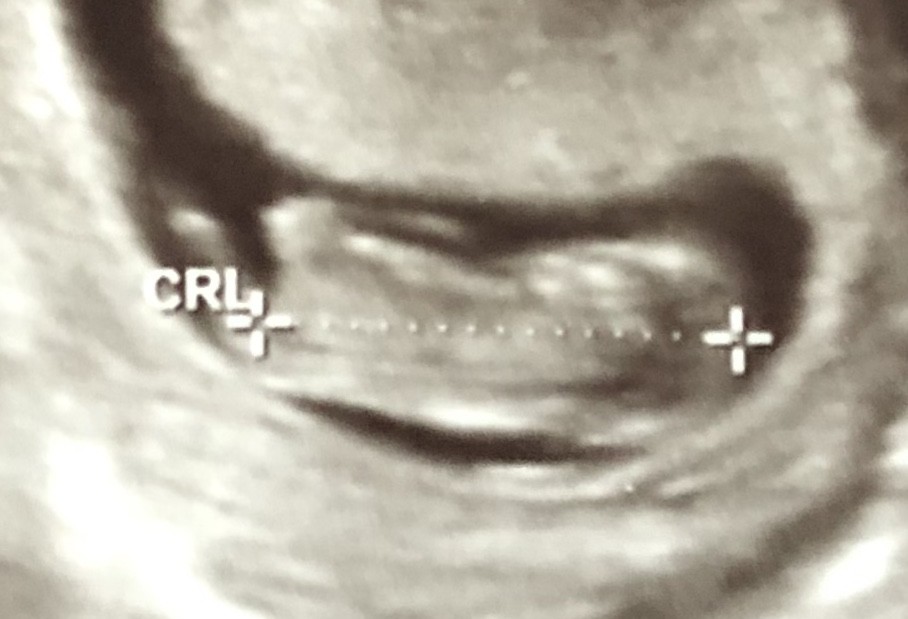

SadmiN ♥ Evli Mutlu Çocuklu ♥ Yönetici 20 Aralık 2019 #683 Malesef ilgili bölüm çok net değil yanlış bi tahminde de bulunmak istemiyorum cepten yakın çekip gönderebilir misiniz bi kaç tane çekin atın lütfen.

SadmiN ♥ Evli Mutlu Çocuklu ♥ Yönetici 20 Aralık 2019 #685 Yani çok net olmamakla birlikte erkek diyebileceğimi düşünüyorum.